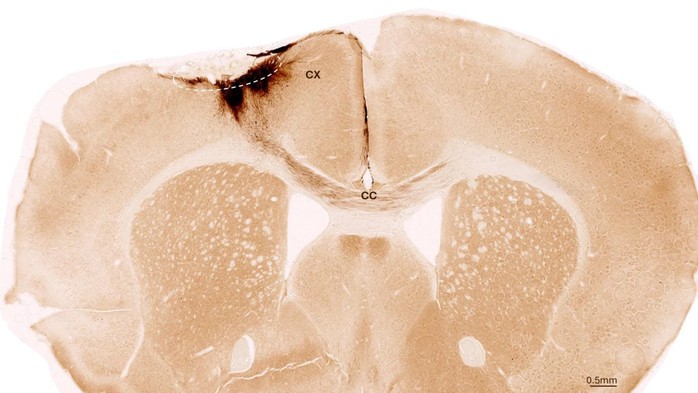

Hình ảnh này chụp cắt lớp não chuột sau đột quỵ và ghép tế bào gốc thần kinh, với vòng tròn nét đứt đánh dấu vùng bị đột quỵ, trong khi các nhánh thần kinh được tạo ra từ tế bào gốc của người được tô màu nâu sẫm - Ảnh: ĐẠI HỌC ZURICH

Nhóm nghiên cứu đã thí nghiệm những con chuột bị đột quỵ và được biến đổi gene để không đào thải tế bào của con người.

Một tuần sau cơn đột quỵ, những con vật này được ghép tế bào gốc thần kinh của người, là loại tế bào có thể biến đổi thành các loại tế bào khác nhau của hệ thần kinh.